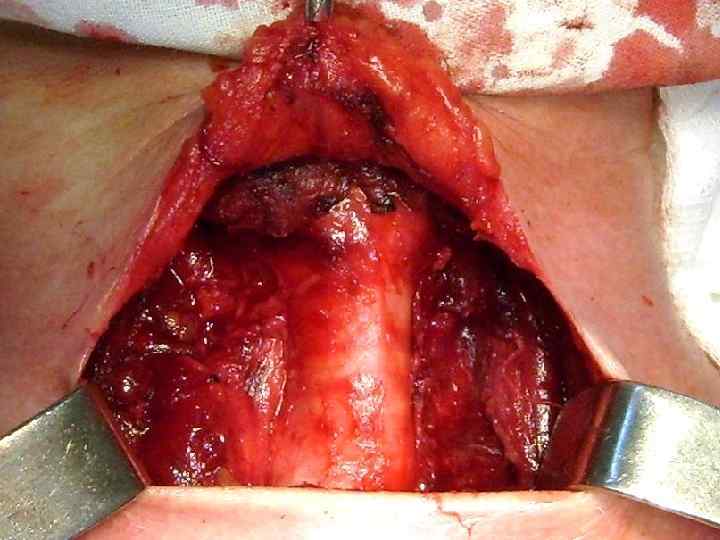

ХИРУРГИЧЕСКОЕ ЛЕЧЕНИЕ ЗОБА

ОСЛОЖНЕНИЯ ХИРУРГИЧЕСКОГО ЛЕЧЕНИЯ ►Поражение возвратного нерва, приводящее к параличу голосовой связки на стороне поражения, как следствие – изменение тембра голоса, сужение голосовой щели, затруднение дыхания. ► Кровотечение. ►Тиреотоксический криз. ► Гипопаратиреоз. ► Рецидив тиреотоксикоза. ► Формирование порочного рубца.